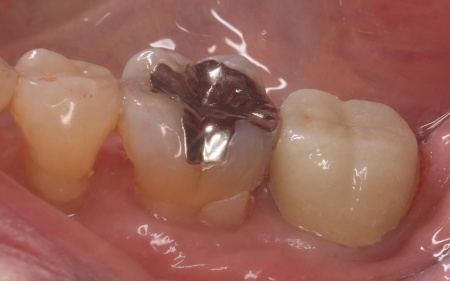

また根管治療後の被せ物には、ジルコニアクラウンを選択しています。

メリット:自然な白さが再現できる。人工ダイヤモンドと呼ばれるほど高い強度と耐久性をもつため、奥歯のような強い力がかかる場所に適している

デメリット:非常に硬いため、噛み合わせの調整が不十分な場合、噛み合う歯に負担をかけるリスクがある

後日、完成したジルコニアクラウンを装着し、歯にぴったりと合っているか、噛み合わせに問題がないかを十分に確認して、治療を終了しています。